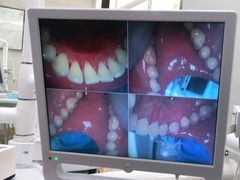

• 牙博士口腔品牌连锁(杨浦店)

• -牙博士口腔品牌连锁(杨浦店)

空空酱 | 21-03-18